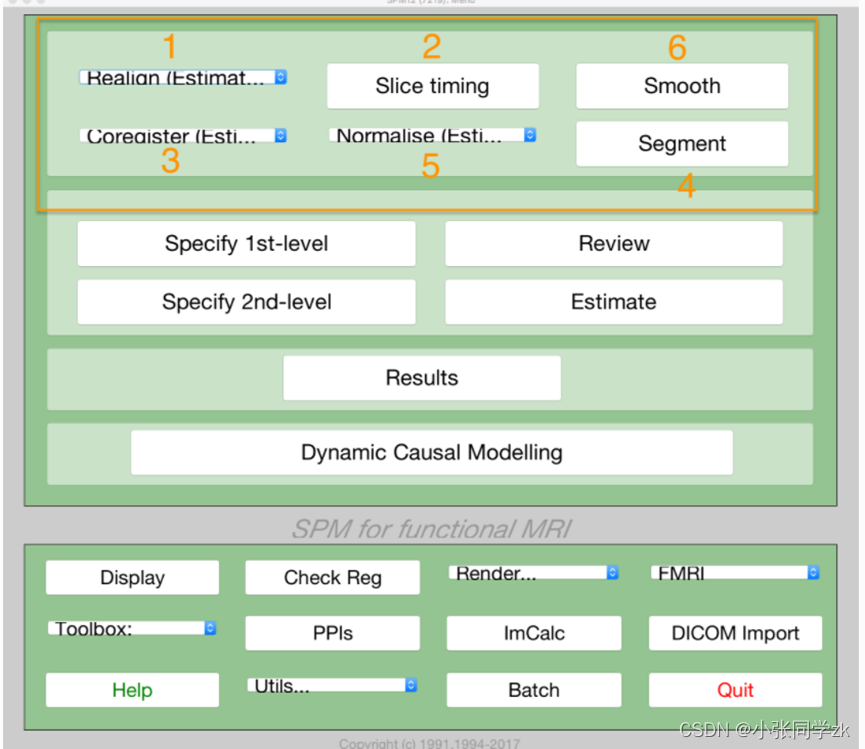

预处理的顺序如下图所示:

!Note:不同的软件包预处理的顺序有所不同,如果我们做的是multi-voxel 模式,则不需用做平滑这一步。